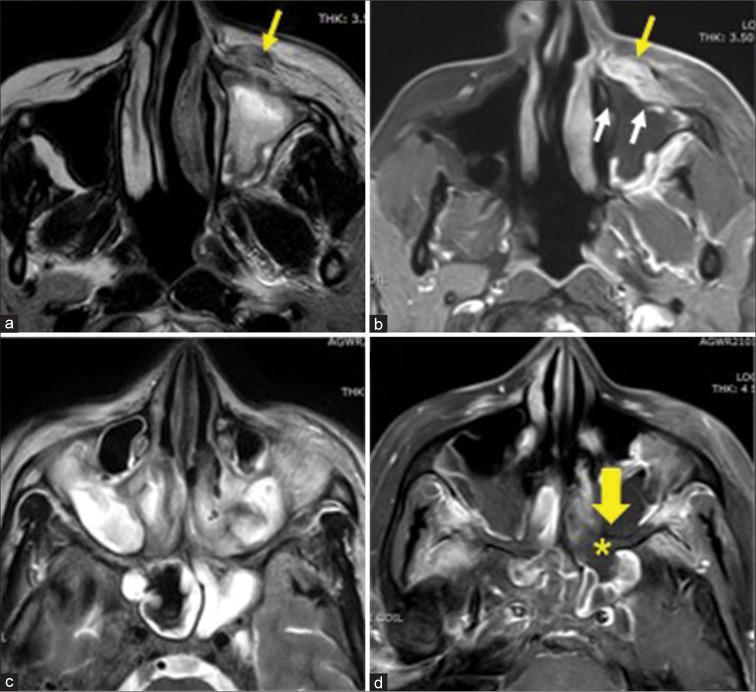

The most frequent MRI finding was T2 hypointensity in the sinonasal mucosa (94%) followed by mucosal necrosis/loss of contrast-enhancement (92.6%). Extrasinosal inflammation with or without necrosis in the pre-antral fat, retroantral fat, pterygopalatine fossa, and masticator space was seen in 91.1% of the cases. Extrasinosal spread was identified on MRI even when the computed tomography (CT) showed intact bone with normal extrasinosal density. Orbital involvement (72%) was in the form of contiguous spread from either the ethmoid or maxillary sinuses; the most frequent presentation being orbital cellulitis and necrosis, with some cases showing extension to the orbital apex (41%) and inflammation of the optic nerve (32%). A total of 22 patients showed involvement of the cavernous sinuses out of which 10 had sinus thrombosis and five patients had cavernous internal carotid artery involvement. Intracranial extension was seen both in the form of contiguous spread to the pachymeninges over the frontal and temporal lobes (25%) and intra-axial involvement in the form of cerebritis, abscesses, and infarcts (8.8%). Areas of blooming on SWI were noted within the areas of cerebritis and infarcts. Perineural spread of inflammation was seen along the mandibular nerves across foramen ovale in five patients and from the cisternal segment of trigeminal nerve to the root exit zone in pons in three patients. During follow-up, patients with disease progression showed involvement of the bones of skull base, osteomyelitis of the palate, alveolar process of maxilla, and zygoma. Persistent hyperenhancement in the post-operative bed after surgical debridement and resection was noted even in patients with stable disease.

Contrast-enhanced MRI must be performed in all patients with suspected AIFRS as non-contrast MRI fails to demonstrate tissue necrosis and CT fails to demonstrate extrasinosal disease across intact bony walls. Orbital apex, pterygopalatine fossa, and the cavernous sinuses form important pathways for disease spread to the skull base and intracranial compartment. While cerebritis, intracranial abscesses, and infarcts can be seen early in the disease due to the angioinvasive nature, perineural spread and skull base infiltration are seen 3-4 weeks after disease onset. Exaggerated soft-tissue enhancement in the post-operative bed after debridement can be a normal finding and must not be interpreted as disease progression.